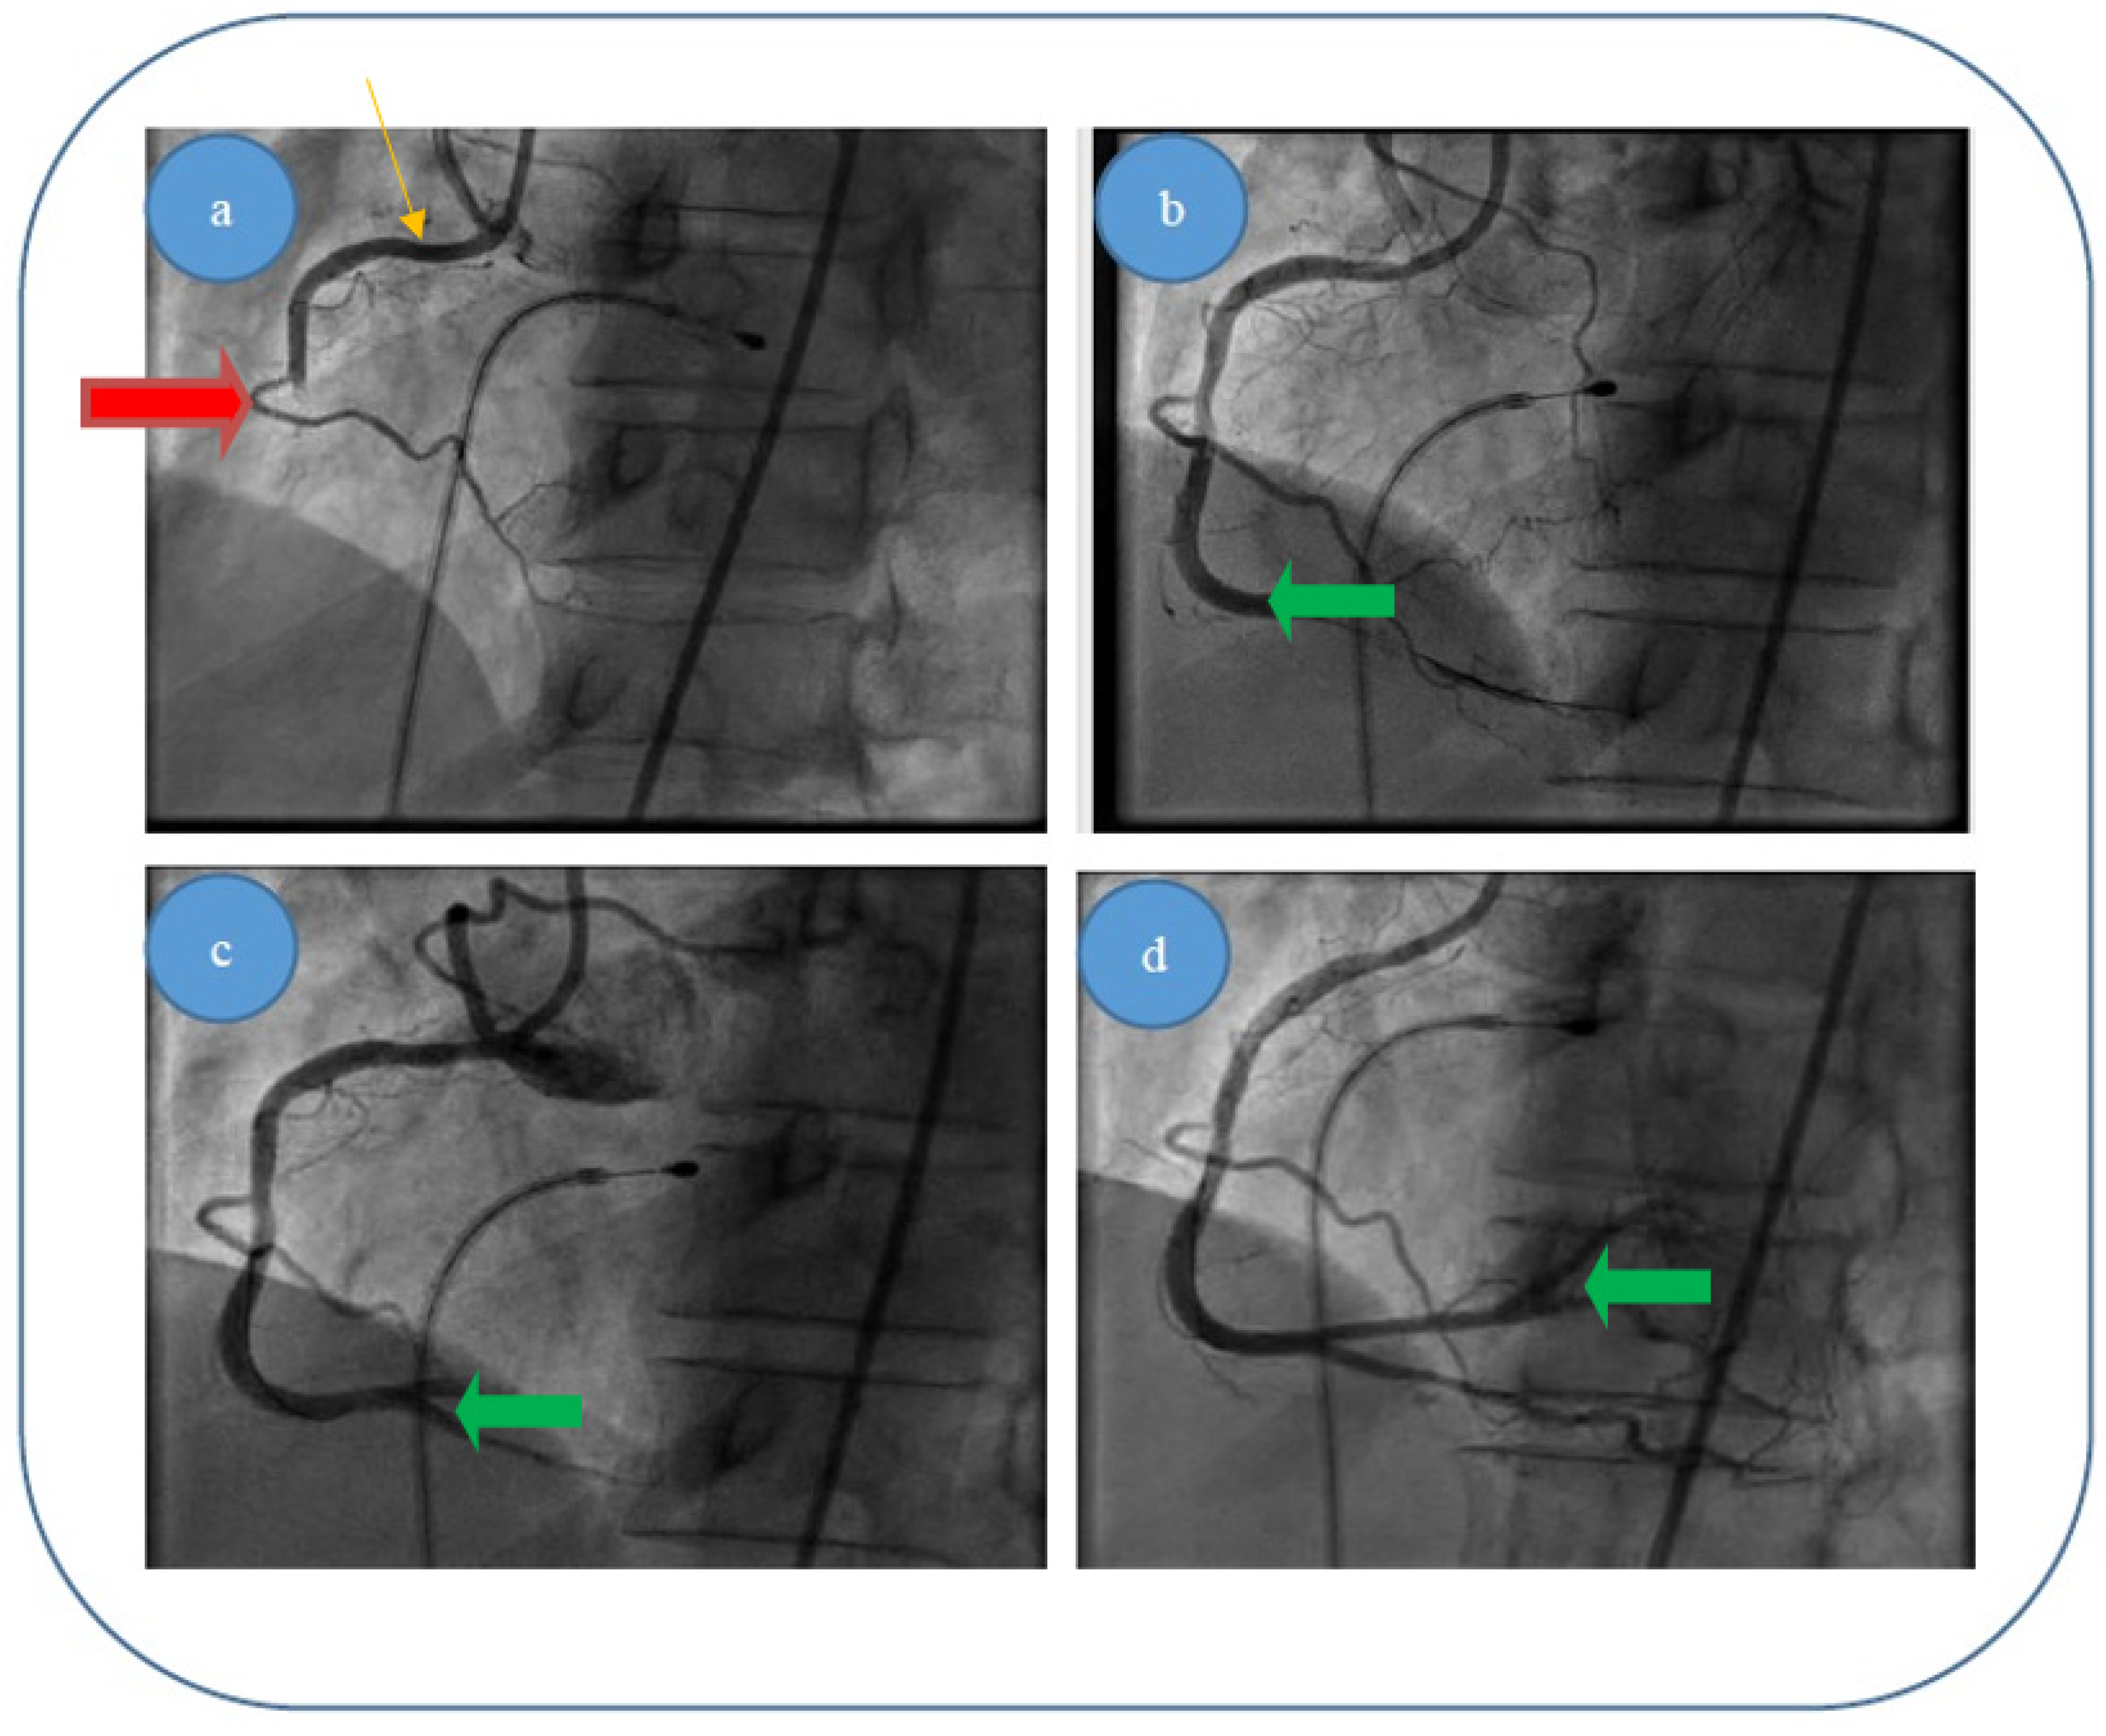

Patient 3, a 61 year-old female patient who was diagnosed with acute inferior and poster lateral ischemia; coronary angiography revealed an acute occlusive thrombus extending from the beginning of right coronary artery segment II to crux (4.5–5 mm diameter and approximately 80–100 mm length), possibly with extensions to right posterior descending artery and poster lateral branches; repeated thrombus aspiration with unsatisfying results in terms of distal TIMI flow (0–1), but with no evidence of significant atherosclerotic disease at the level of culprit zone—see Figure 8a–d.

Figure 8. (ad). Acute thrombus formation (red arrow) in an apparently healthy artery (orange arrow) with no evidence of plaque dissection—different interventional approach stages for patient 3: (a) blood flow before thromboaspiration; (c,d) blood flow returning to normal after thromboaspiration/removal of thrombus (green arrow). (b) Explanation.